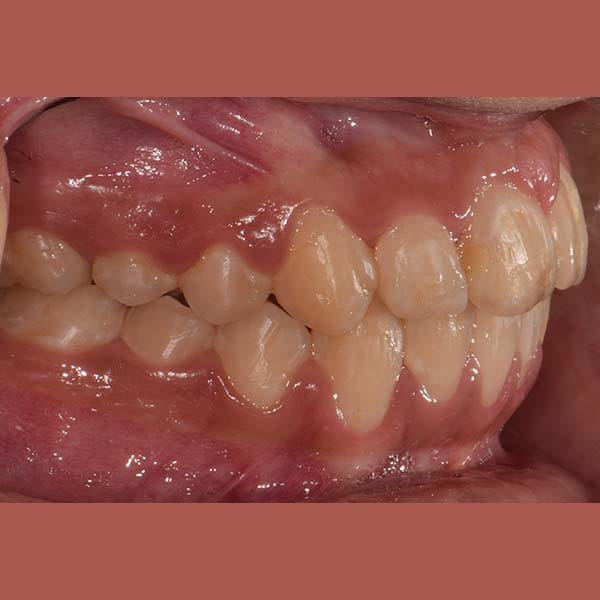

بعد شرح أن قلع الأسنان يكون ضرورياً أحياناً، وبعد الفحص الدقيق، طمأن الدكتور خالد الكاتب الأم بأنه لحسن الحظ، حالة ابنتها تسمح بالعلاج دون قلع. اعتمدت الخطة على توسيع الفكين لفتح مسافة كافية لرصف الأسنان. تم اختيار تقويم الدايمون (ذاتي الربط) لهذه المهمة، حيث يعتبر مثالياً لهذا النوع من المعالجات التي تتطلب توسيعاً فعالاً.

كما تظهر الصور، نجحت الخطة العلاجية في رصف الأسنان بشكل ممتاز وتحقيق ابتسامة جميلة ومتناسقة. وكالعادة، أصبح بإمكان صديقتنا الشابة أن تبتسم لوالدتها ولكل من حولها بثقة وسعادة.